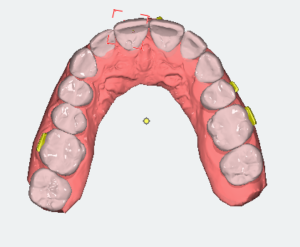

Analizę przemieszczeń zębów w zakresie mezjalizacji trzonowców w szczęce oraz przemieszczenie przedtrzonowca górnego rozpoczęto dopiero po uzupełnieniu zlecenia o analizę zdjęcia panoramicznego oraz badań dodatkowych. Opisano trzy opcje leczenia tego pacjenta. Pierwsza propozycja obejmowała brak mezjalizacji d. 26 i d.27; dystalizację w zakresie wybranych zębów. Druga propozycja obejmowała minimalną dystalizację drugiej ćwiartki łuku zębowego. Trzecia propozycja obejmowała sekwencyjną mezjalizację d. 26 oraz d. 27.

Cyfrowy plan leczenia przeanalizowano pod kątem osiągnięcia klinicznego celu zaplanowanego przez lekarza. Zaplanowana na cyfrowym planie leczenia mezjalizacja nie uwzględniała rekomendowanego sekwencyjnego przemieszczania zębów. Oznaczało to bardzo mało prawdopodobne zajście tych ruchów w jamie ustnej u pacjenta. Opisano lekarzowi, na czym polega sekwencyjna mezjalizacja zębów i jak zaprojektować ją w nowym planie leczenia. Zwrócono uwagę, że tego typu przemieszczenia zębów są bardzo wymagające, dlatego lekarze do zwiększenia możliwości ich zajścia stosują np. miniimplanty ortodontyczne. Opisano wpływ ilości i jakości attachmentów na zwiększenie przewidywalności ruchów zębowych.

- Zmodyfikować sekwencje mezjalizacji trzonowców.

- Plany leczenia dzielić na części, w których przemieszczane są pojedyncze zęby, a nie wszystkie zęby w maksymalnych zakresach jednocześnie.